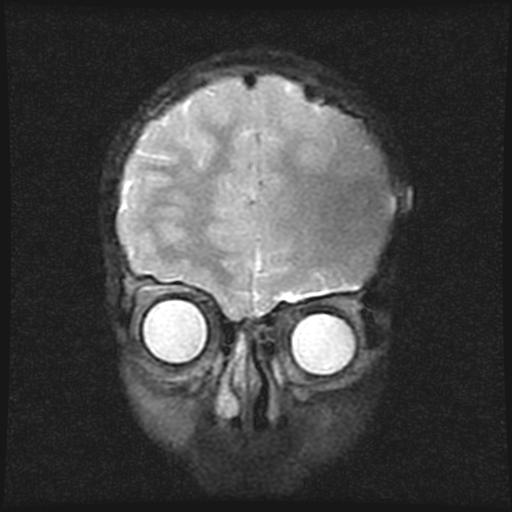

标题: PED0377: 6岁小儿,左侧视神经瘤术后 [打印本页]

6岁小儿,左侧视神经瘤术后。现左侧视力减退。